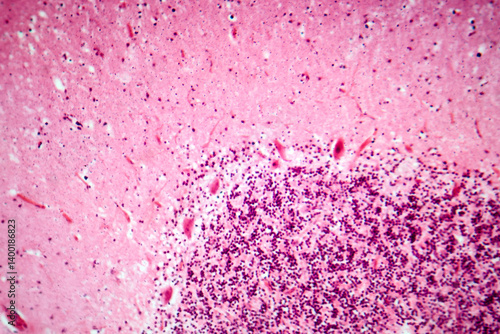

Mikrofotografi - Plakater, Poster, Billeder på lærred